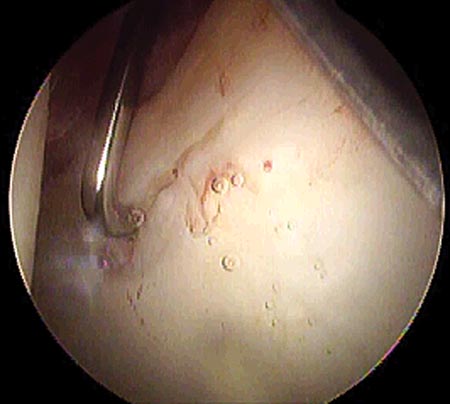

Se utilizaron para la reinserción, arpones biodegradables con sutura simple de alta resistencia. Se colocaron entre uno y tres arpones según la extensión de la lesión.

No se usaron nudos corredizos, debida a la profundidad en la localización de la cadera, y el pasaje de la sutura se hizo por la base de la lesión (Fig. 11 y 12).28,29

Figura 11: Pasaje de la sutura por la base de la lesión./ Figura 12: Reparación estable del labrum.